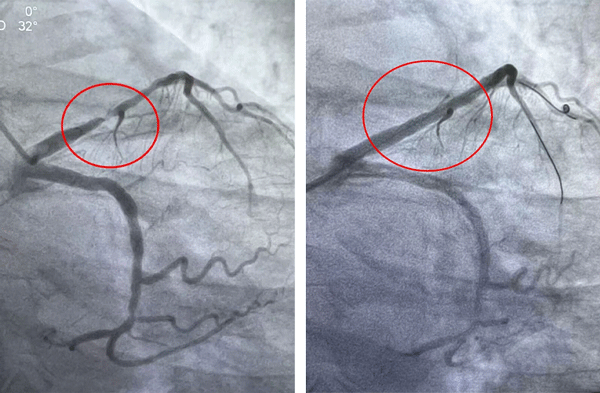

▲术前 ▲术后

其中,31岁的关先生因恶心、呕吐等消化道症状就诊,经检查确诊为心肌梗死,急诊冠脉造影提示右冠脉闭塞。团队迅速启动绿色通道,及时开通梗死相关血管并植入支架,患者转危为安。